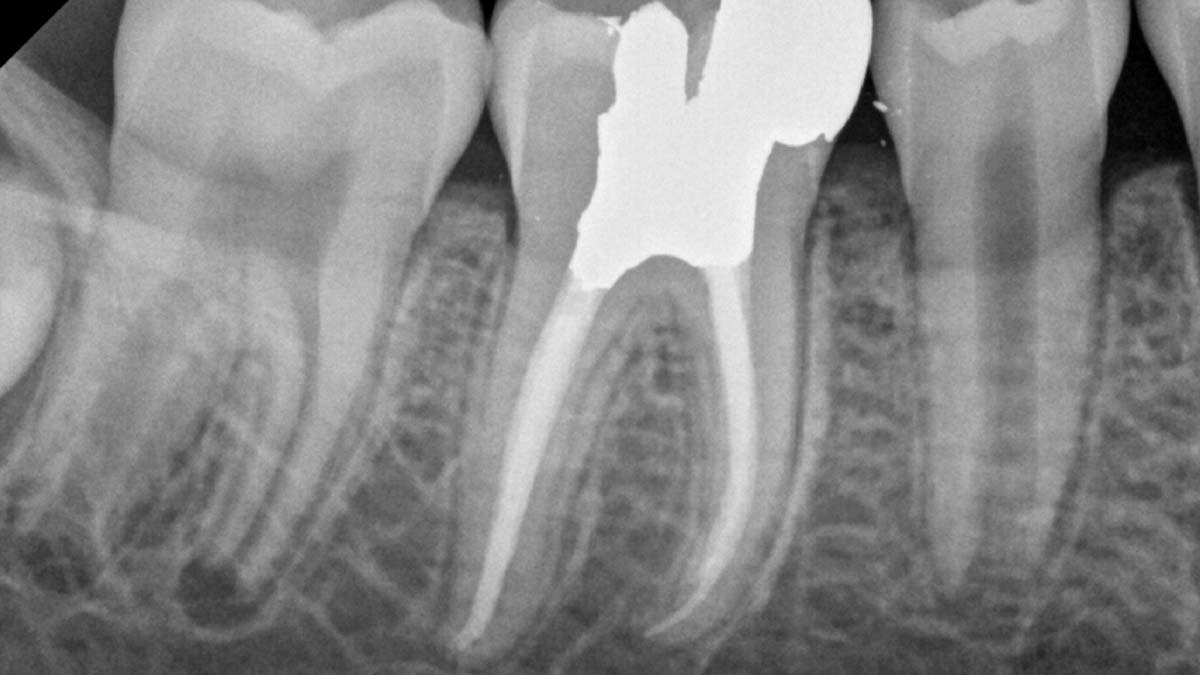

On the left: Using different formulations of gutta-percha in one case can cause varying degrees of opacity.

Image courtesy of Dr. Phillip Bell, Mooresville, NC

On the right: Gutta-Smart and Conform Fit feature the same advanced gutta-percha for radiographic consistency.

Image courtesy of Dr. Nathaniel Behrents, Fayetteville, AR